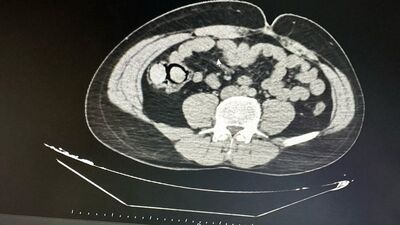

Şüphelilerin hastanede yapılan muayenelerinde, midelerinde toplamda 10 parça halinde 113 gram metamfetamin maddesi ele geçirildi. Şüphelilerin midelerindeki uyuşturucu paketleri, hastanede yapılan işlemle çıkarıldı.

Fotoğraf, DHA tarafından servis edilmiştir.